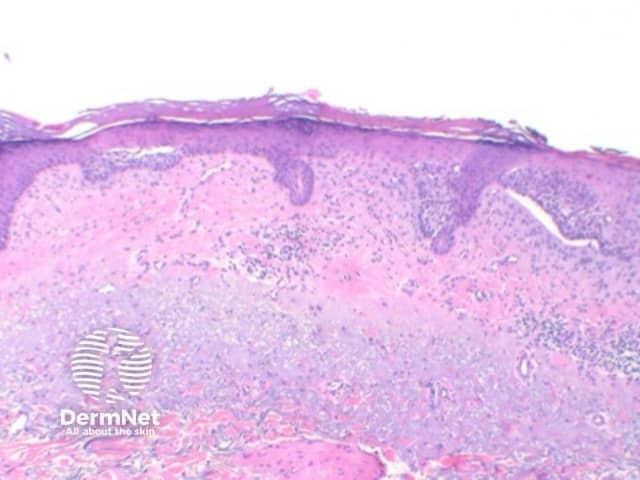

The key feature of basal cell carcinoma at low power magnification is of a basaloid epithelial tumour arising from the epidermis (figure 1). The basaloid epithelium typically forms a palisade with a cleft forming from the adjacent tumour stroma (figure 2). Centrally the nuclei become crowded with scattered mitotic figures and necrotic bodies evident (figure 3). A useful distinguishing feature from other basaloid cutaneous tumours is the presence of a mucinous stroma (figure 4). Some tumours may also show foci of regression, seen as areas of eosinophilic stroma with lack of basaloid nests.

Figure 1

Nodular BCC: The tumour forms a solid tumour nodule or nodules which may extend into subcutaneous tissues. Cartilaginous invasion is unusual (figure 1).